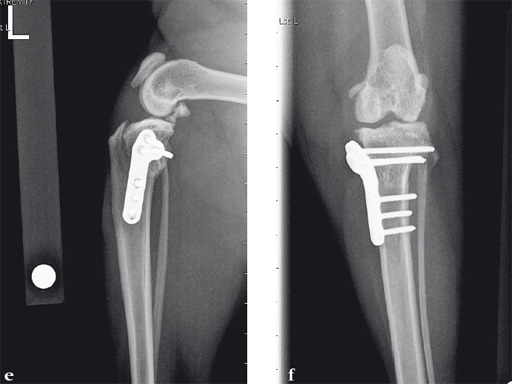

Case 1: Cocker Spaniel

(Case provided by Brian Beale, Houston, USA)

An 11-year-old female, spayed, 13.6 kg cocker spaniel had a complete tear of the left cranial cruciate ligament. A 2.4 mm TPLO plate was perfect for this dog due to the excessive slope of the tibial plateau (30) and the size of the dog. Three 2.4 mm locking screws were used proximally and three 2.4 mm cortical screws were used distally. The contour of this plate matches the contour of the bone almost perfectly. The plate is also designed to optimize the angle of the proximal screws so that they engage the most dense and thickest bone and avoids penetration of the stifle joint.

Case 2: Cat

A 10-year-old female, spayed, 6.0 kg cat had a partial tear of the left cranial cruciate ligament, meniscal mineralization, and a medial meniscal tear. The cat was treated with a partial meniscectomy and TPLO . A 2.0 mm TPLO plate was perfect for this cat due to the slope of the tibial plateau (25) and the size of the cat. Three 2.0 mm locking screws were used proximally and three 2.0 mm cortex screws were used distally. The contour of this plate does not perfectly match the contour of the proximal tibia, but use of locking screws in this segment avoids any potential angulation of the segments as the screws are tightened. The cat healed uneventfully and returned to normal function.